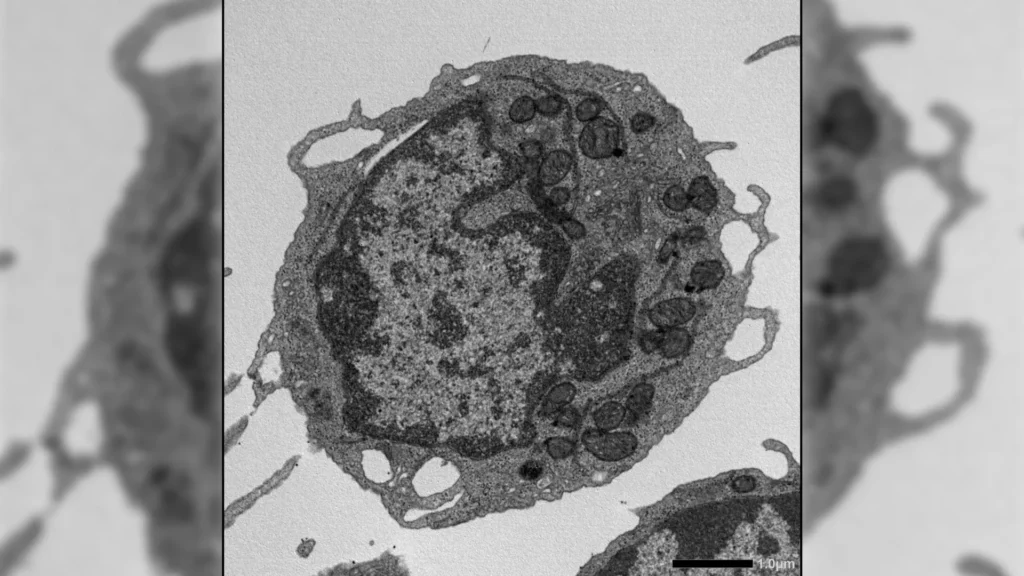

Técnicas adicionais forneceram insights mais profundos, incluindo citometria de fluxo, expansão ex vivo, RNA-seq, ensaio para cromatina acessível a transposase (ATAC-seq), imagens de alta resolução, testes metabólicos e estudos detalhados sobre mitocôndrias. Juntas, essas abordagens permitiram que os pesquisadores examinassem como a MLKL afeta as CTHs em múltiplos níveis.

Quando ativada sob estresse, a MLKL se movia temporariamente para as mitocôndrias, as estruturas que geram energia dentro das células. Ali, causou danos ao reduzir o potencial da membrana, alterar a estrutura mitocondrial e diminuir a produção de energia. Esses efeitos levaram a características-chave do envelhecimento nas CTHs, incluindo a redução da capacidade de renovação, diminuição da produção de células linfoides e uma mudança na produção para células mieloides.